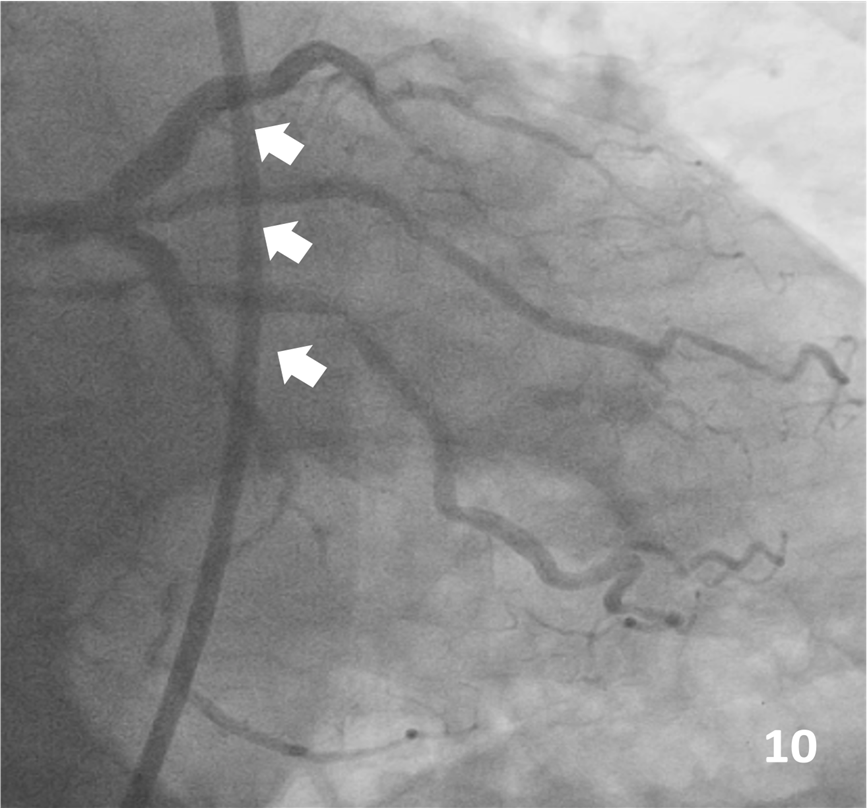

Final IVUS showed adequate expansion and no edge dissections (Figure 9). The final angiographic result is shown in Figure 10. There were no complications at all during the procedure, and the patient was discharged 3 days later.